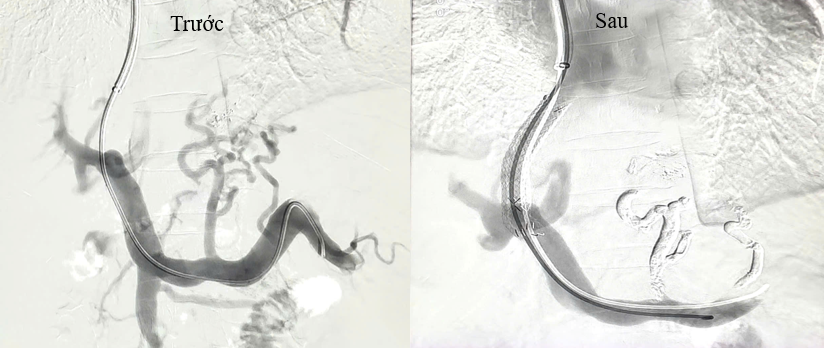

Ekip của Tiến sĩ Trần Quang Lục đã can thiệp cho người bệnh bằng kỹ thuật TIPS với sự hỗ trợ của hệ thống máy chụp mạch số hóa xóa nền DSA và các trang thiết bị hiện đại. Toàn bộ quy trình kỹ thuật được thực hiện trong lòng mạch máu với một vết chọc rất nhỏ tạo đường vào ở tĩnh mạch cổ. Sau khoảng 1 giờ can thiệp, các bác sĩ đã đặt một stent phủ vào trong gan, làm giảm áp lực tĩnh mạch cửa và nút tắc hoàn toàn các búi giãn tĩnh mạch thực quản. Sau 2 ngày theo dõi, người bệnh đã hoàn toàn ổn định, đi ngoài phân vàng, tình trạng chướng bụng giảm đáng kể, các xét nghiệm cải thiện tốt và được ra viện điều trị theo phác đồ tại nhà.

Hình ảnh trước và sau khi đặt stent TIPS trong gan và nút tắc các búi giãn tĩnh mạch thực quản.